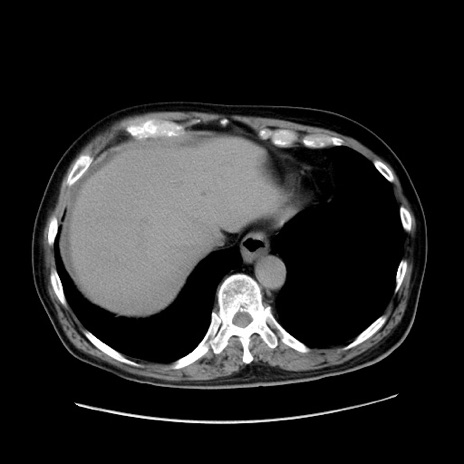

冠状断像

症例30(横断像)

【症例】80歳代男性

【主訴】臍周囲痛

【現病歴】約6時間前から臍下部痛が出現。次第に腹部膨隆・背部痛も生じてきたため来院。背部痛の場所は変化しない。

【既往歴】腎盂腎炎

【身体所見】意識清明、BT 36.3℃、BP  131/87mmHg、P 87bpm、SpO2 100%(RA)、臍周囲自発痛・圧痛あり、反跳痛なし、自発痛部位に一致して板状硬あり、腹部膨隆、腸雑音減弱、CVA tenderness両側陰性。

【データ】WBC 19600、CRP 0.33